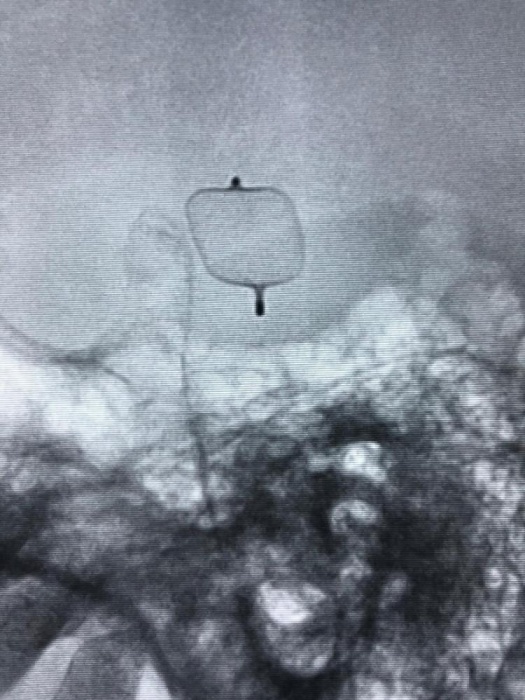

أجرى مستشفى الملك حمد الجامعي عملية جراحية الأولى من نوعها لحالة شديدة الخطورة كانت تعاني من شريان منتفخ في المخ على وشك الانفجار.وكان المريض قد تدهورت حالته الصحية بعد أن شخص الأطباء بمستشفى السلمانية الطبي حالته بنزيف في المخ، وأوصوا بسرعة إجراء عملية جراحية لمعالجة الشريان المنتفخ قبل انفجاره.واستجابت إدارة مستشفى الملك حمد جامعي على الفور للحالة المرضية وتدخل فريقها لإجراء الجراحة الخطيرة للمريض.واستقرت حالة المريض الصحية في الوقت الحالي، وامتثلت حالته للشفاء بعد أن انقذت العناية الآلهية وسرعة ومهارة الفريق الطبي بمستشفى الملك حمد الجامعي لحياته.

"الملك حمد الجامعي" ينقذ حياة مريض من انفجار شريان بالمخ